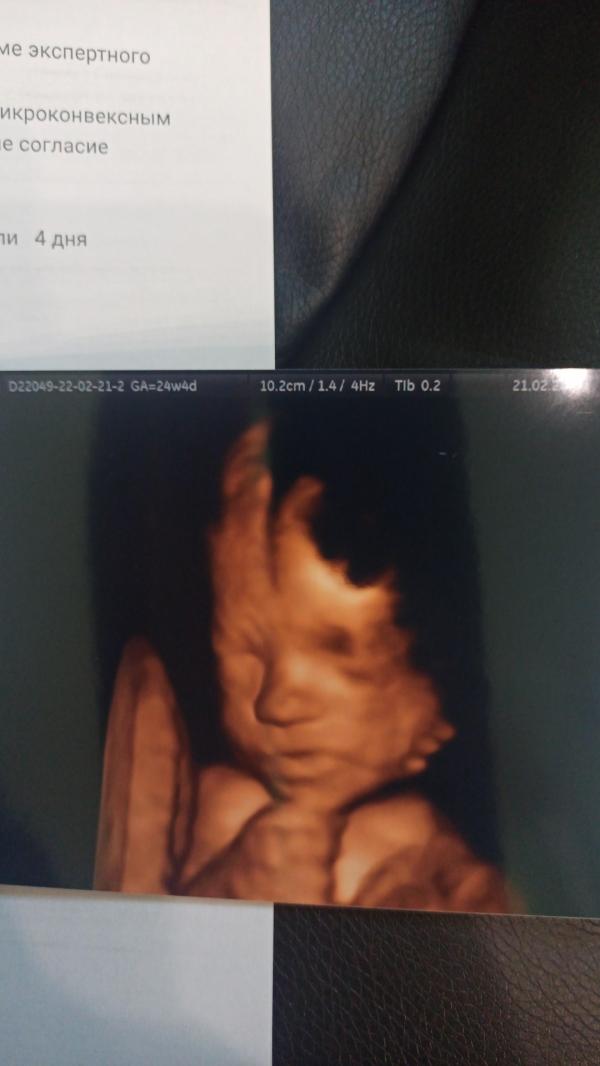

Всё хорошо, развиваемся по сроку, ножки и ручки так и остаются на пару-тройку недель длинннее😇😃🤏 плацента выще зева на 8см, доплер, воды - N. Играла с пуповиной весь сеанс, активно шевелилась, но дала врачу всё померить и посмотреть))) под конец и пуповинку от лица убрала, умница 🌺💙❤

Нос как у братьев - один в один ❤